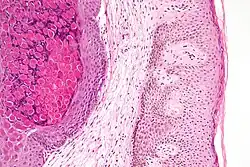

Histologically, molluscum contagiosum is characterized by molluscum bodies in the epidermis, above the stratum basale, which consist of large cells with abundant granular eosinophilic cytoplasm (accumulated virions) and a small peripheral nucleus.[20]

Low magnification micrograph of a molluscum contagiosum lesion

Low-magnification micrograph of molluscum contagiosum, H&E stain

High-magnification micrograph of molluscum contagiosum, showing the characteristic molluscum bodies, H&E stain